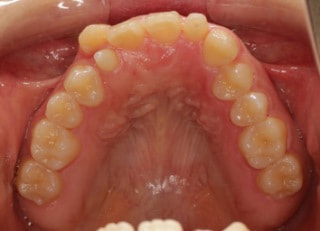

治療後(2年11ヶ月後)